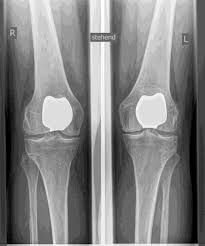

Artificial knee joints are divided into full and partial prostheses. I will carefully check which prosthesis is suitable for you based on a clinical examination and on X-rays or MRI scans.

Partial knee replacement is possible in all areas of the joint, but is most commonly performed on the inside of the knee joint and is often referred to colloquially as a sled prosthesis. Similar to a full prosthesis, the defective cartilage is replaced with a new surface and a plastic inlay is inserted in between. For a partial prosthesis, all ligament structures, especially the cruciate ligaments, must be largely intact.